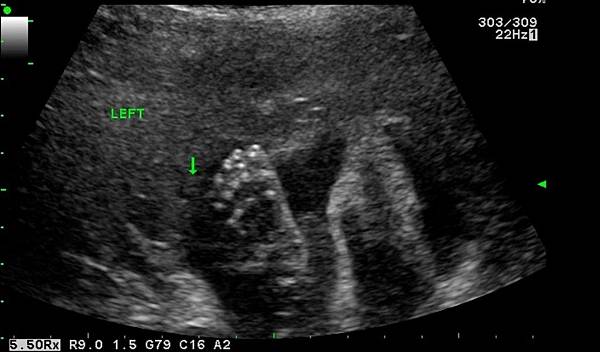

不過醫生照一照就說小孩有"脈絡叢囊腫", 但馬上又murmur說~"不過你已經做過染色體檢查 (NIFTY PLUS)了~應該還好" 可是你知道愛擔心媽媽如我, 聽到醫生講了個關鍵字~感覺出來像是不好的字眼~~~!!!! 馬上就開始擔憂到底是啥東西啊啊啊啊!!!! 馬上google 脈絡叢囊腫看到以下資訊 :

脈絡叢囊腫是指於孕齡在14~24周胎兒發育中超聲檢查發現的側腦室脈絡叢散在的、直徑≥3mm的小囊腫。

90%以上胎兒脈絡叢囊腫在妊娠26周以後消失,僅少數呈進行性增大。

檢出脈絡叢囊腫時應結合其他臨床資料,進一步行羊膜腔穿刺羊水細胞培養或臍帶穿刺取臍血培養,或者無創DNA。

以除外18-三體、21-三體等染色體異常。

正常的胎兒也可以出現脈絡叢囊腫,但大多26周後消退。

如果26周後還不消退,而且是雙側的,孩子生後應該做顱腦的檢查及臍血細胞的染色體檢查。

如果能夠消失,就不會出現壓迫和顱壓增高,出生後的智力或其他方面也不會因「脈絡叢囊腫」而受到影響。